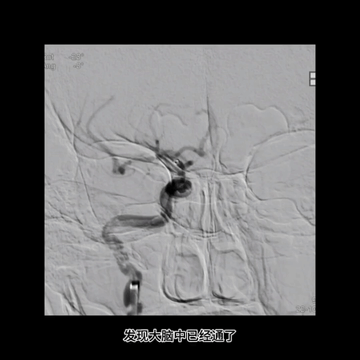

微导丝配合下,微导管首先通过闭塞血栓位置进入M2下干,导丝跟进把微导管送至M2下干中远段,造影证实位于真腔后,送入取栓支架Trevo 4*20mm,释放支架后恢复前向血流,支架完全覆盖病变,血栓负荷较大。

5F中间管负压下退至颈内动脉末端时,经长鞘造影示右侧MCA再通。

持续负压下回收中间管,后造影示颈内动脉后交通位置闭塞,提示血栓较大且坚硬,从5F中间管头端脱落。